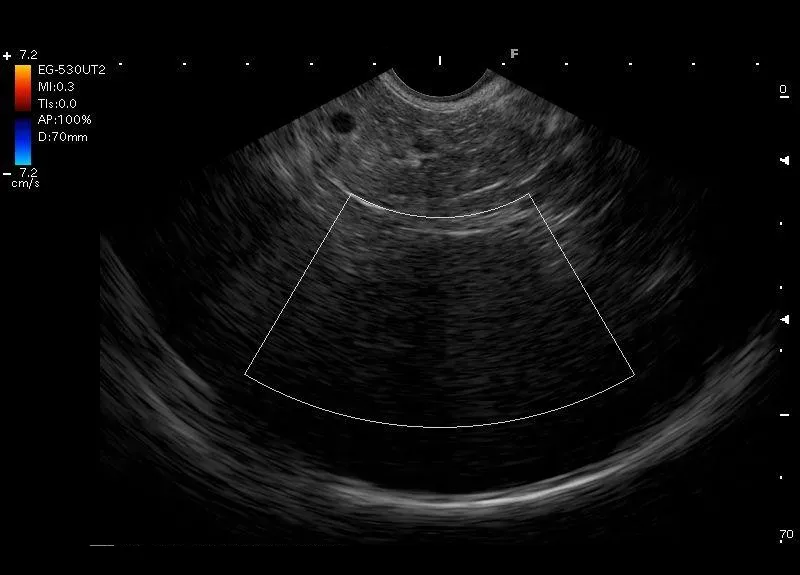

Zobrazowana przez głowice EUS przyłożoną w żołądku - śledziona